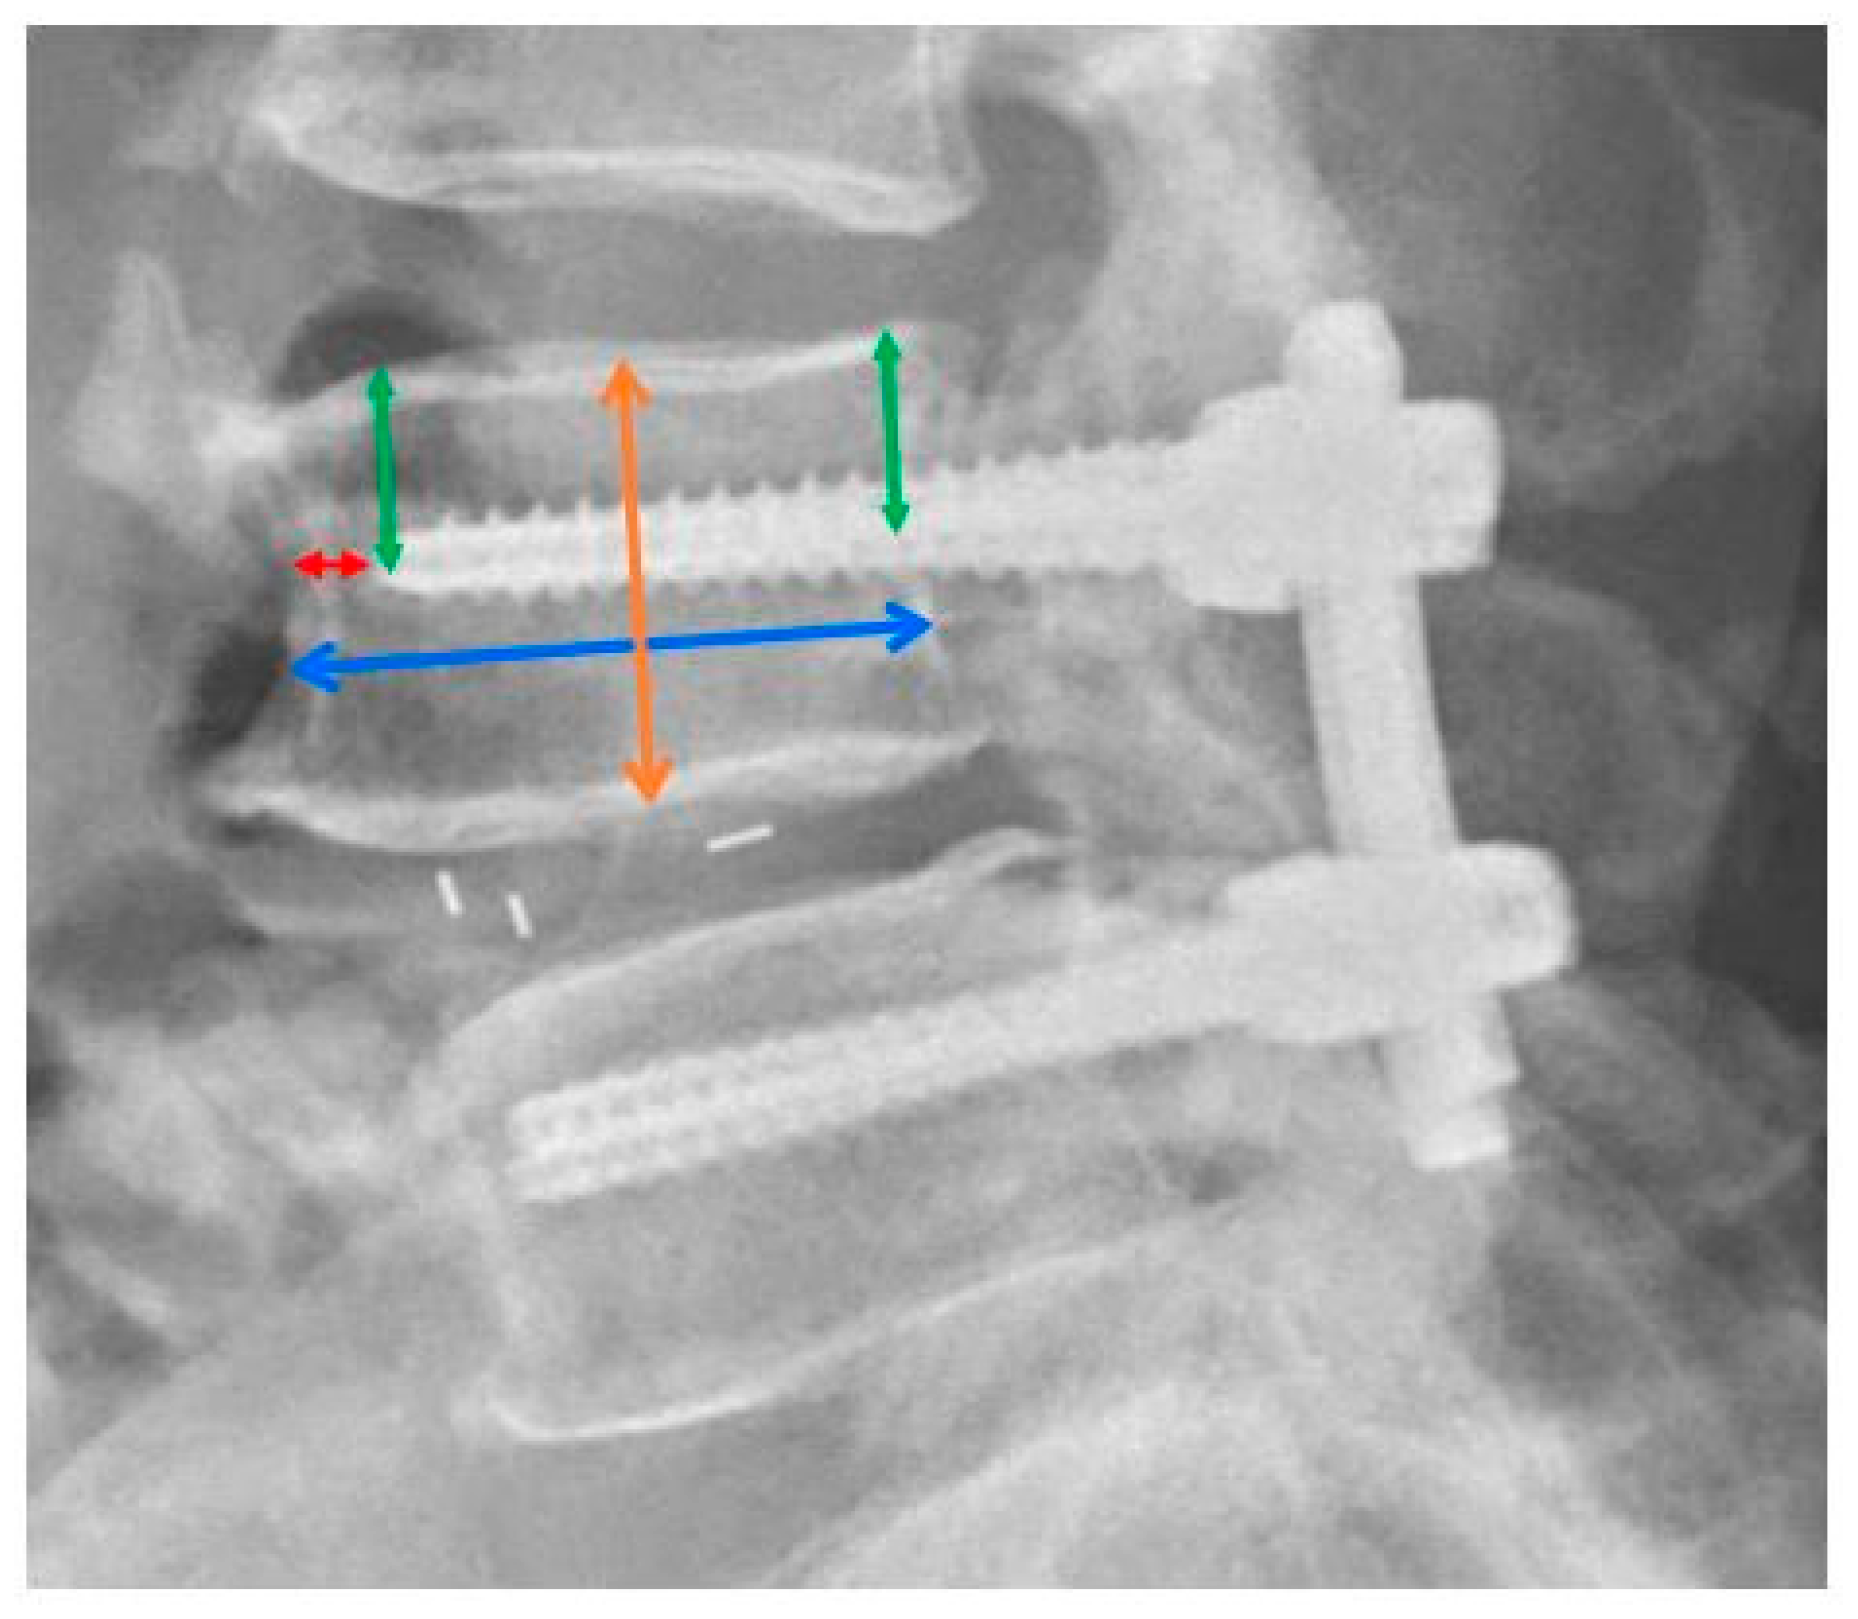

2.4. Measurements of Radiographic Parameters

2.5. Definition of Screw Loosening and Cage Subsidence

| Distance from pedicle screw to upper endplate/vertebral body height | 0.39 [0.36, 0.42] | 0.35 [0.29, 0.37] | <0.001 * |

| Distance from screw tip to anterior cortex/vertebral body AP diameter | 0.14 [0.06, 0.22] | 0.12 [0.04, 0.19] | 0.124 |

| Distance from pedicle screw to upper endplate/ vertebral body height | 0.40 [0.38, 0.41] | 0.37 [0.34, 0.41] | <0.001 * |

| Distance from screw tip to anterior cortex/ vertebral body AP diameter | 0.16 [0.06, 0.25] | 0.13 [0.05, 0.20] | 0.100 |